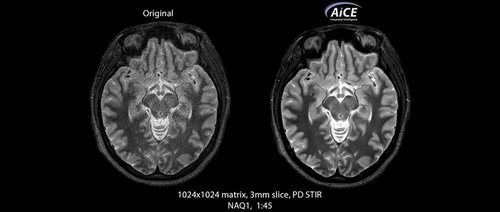

KI-optimiertes Arbeiten und modernste 3T-Technologie machen den Vantage Galan 3T von Canon Medical aus. Canons KI-Anwendung AiCE, kurz für Advanced intelligent Clear-Imagequality Engine, entfernt intelligent das Rauschen und führt zu einer Verbesserung des SNR (Signal-Rausch-Verhältnis). Mit Hilfe der Deep Learning Technologie gelingen besonders klare und deutliche Bilder. Insgesamt ermöglicht die KI-Unterstützung des Vantage Galan 3T somit nicht nur eine höhere Auflösung der Bilder, sondern verkürzt in vielen Fällen auch die Aufnahmezeit.

• AiCE KI-Technologie zur Entfernung von Bildrauschen und Verbesserung des SNR